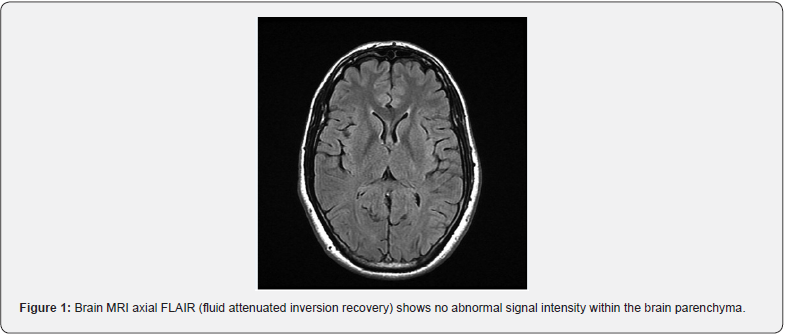

The neurological examination was positive for bilateral papilledema of grade 3 (worsened from the last exam two months ago). Visual acuity was decreased; light perception on the left eye and counting fingers on the right eye. Brain CT was normal. Brain MRI with MRV documented a filling defect in the superior sagittal sinus and torcular herophili, suggesting chronic thrombosis with the thin flow within the superior sagittal sinus and good recanalization within the transverse sigmoid sinuses as well as internal jugular veins (Figures 1 & 2). No new lesions were suggestive of a flare-up of Behçet’s disease. Prominent subarachnoid spaces along the optic nerves were worrisome for increased ICP. ESR (erythrocyte sedimentation rate) and CRP (C-reactive protein) were normal, and INR was therapeutic. An ophthalmologist’s examination documented severe bilateral papilledema with no uveitis.